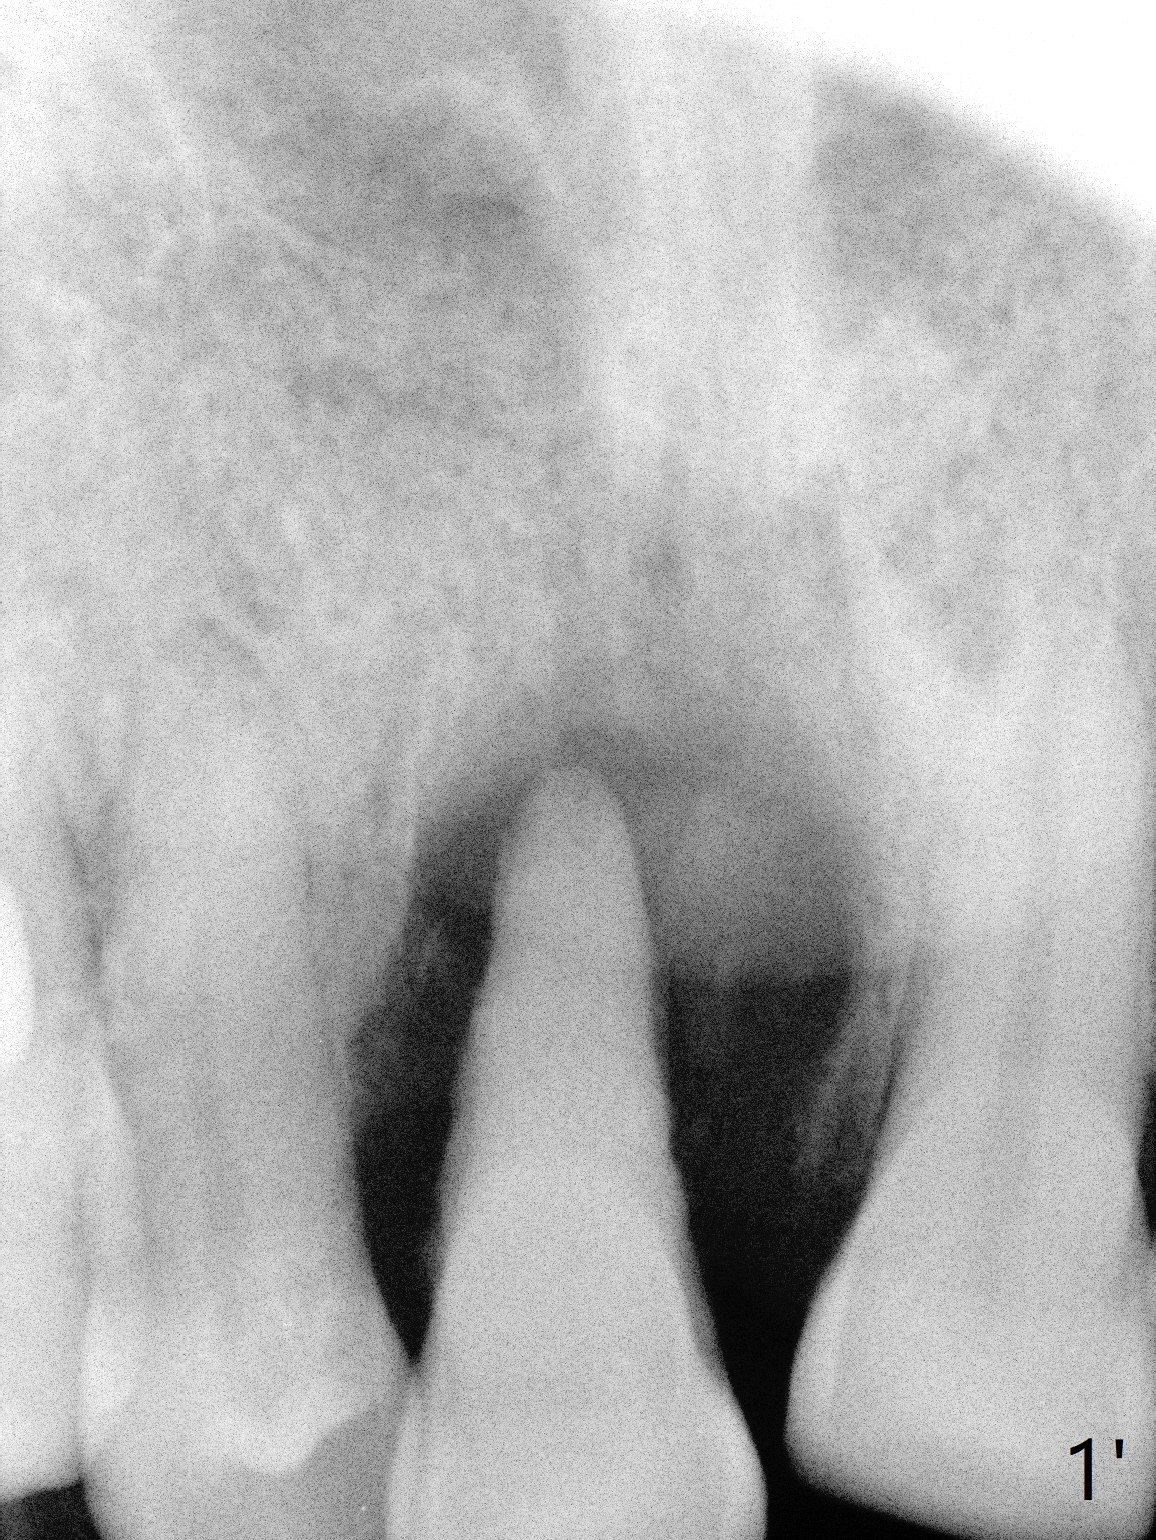

A 69-year-old man (ex-soldier) had the tooth #8 extracted for a flipper nearly 8 years earlier (Fig.1 (obliterated canal)). A denture tooth is added at #14 after extraction in NY a few years later (Fig.2). In spite of sufficient bone width at #8, a 2.5x10 mm mini implant will be chosen to reduce the chance of palatal thread exposure (Fig.3 P). A 5x8.5 mm implant will be placed at #14 to achieve enough stability and not cause sinus complication (Fig.4). Take preop photos to show the anterior deep overbite and overjet. In fact the patient canceled the surgery. Two years later, he returns with history of right TMJ dislocation, which may be related to reduced mastication efficiency and partial edentulism (Fig.5,6).